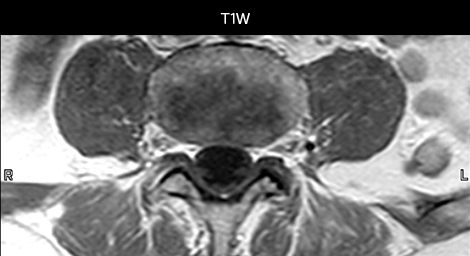

To minimize the time taken to perform scans, rapid MRI examination protocols (ExamCards) were developed, shortening the total scanning time to even less than 10 minutes in some exams. Techniques like mDIXON (modified DIXON) are used for robust capturing of fat-free MRI images in a hectic ED environment.

“We use mDIXON TSE extensively in our spine imaging in the emergency room,” says Dr. Karis. “It’s particularly nice in that it is very robust with regard to susceptibility type of problems that would come up with traditional spectral fat-saturated images; these problems are essentially eliminated with the mDIXON technique. In our ED environment it’s really nice to have the fat-free imaging that goes along with the mDIXON technique.

“For the thoracic and cervical spine routine non-contrast exam, for example, we perform one mDIXON T2 TSE sequence, which provides us with two outputs: the fat-and-water-together T2-weighted images, as well as the water-only sagittal T2-weighted images. And then we also perform an axial gradient echo exam.”